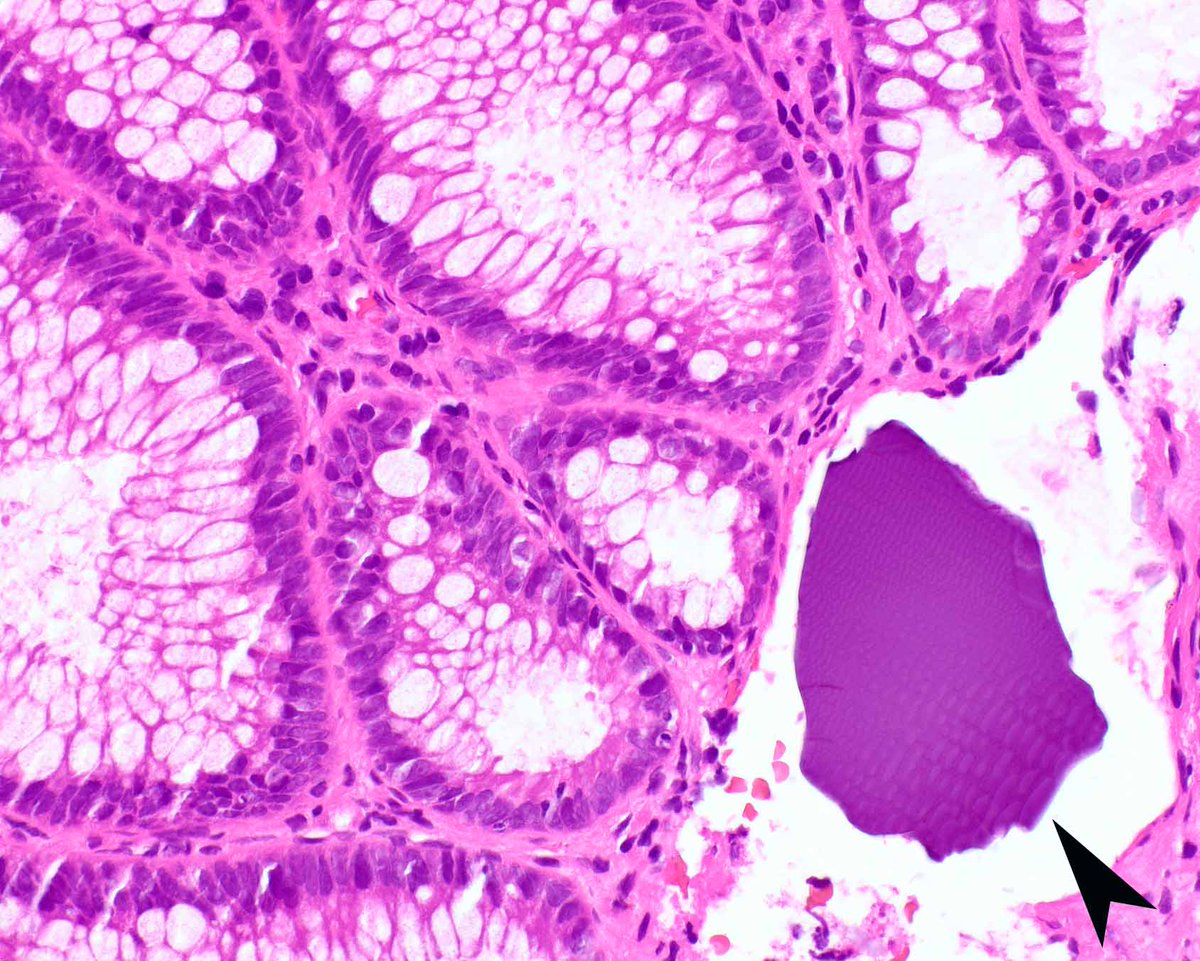

Adenoma accompanied by sodium polystyrene sulfonate (Kayexalate) without mucosal injury. Recent data show a limited association with mucosal injury, an issue in the past when it was administered in hypertonic sorbitol. Note the cracked appearance of the crystals. PMID: 39103605